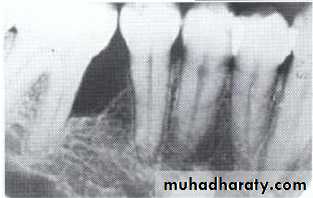

Paramolar blocking the eruption of 3rd molar.

Distodens or distomolarParamolar